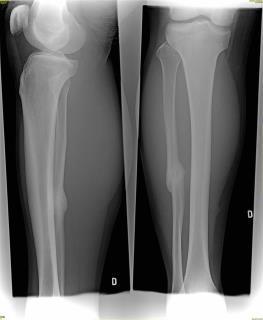

Pro větší náhled klikněte na obrázek

Dobrý den,v listopadu jsem si při fotbalovem treninku zlomil lytkovou kost. Dva měsíce jsem sní kulhal že mam nohu jen nakoplou. V lednu jsem sel k lekari, který mi oznámil že noha je zlomena. Řekl že buď berle nebo sadra. Vzal jsem si berle a na nohu jsem nenaslapoval. Po měsící jsem byl na kontrole a bylo mi řečeno že můžu pomalu začít s treninkem. Ze začátku bylo vše ok, ale později při zátěži mě noha začala bolet. Šel jsem znovu na kontrolu a doktor mi řekl že by se to mělo zhojit samo. Dal jsem si dalsi mesic bez fotbalu a nyni jsem opet zacal trenovat. Po jednom treninku a jednom zapasu me noha zacina opet bolet. Nevim jestli je to normalni ze me to takhle boli. Jediné co mi pomáhá je Ibalgin - stím mohu hrát fotbal. Mam strach abych nemusel na najaky radikalnejší zákrok, který by mě vyřadil z práce. Pokud neběhám je noha v pořádku a skoro vůbec jí necitím jakmile ale začnu trenovat noha mě bolí. Vím že někdo řekne ať nehraju tedy fotbal ale on mi docela finančně pomáhá a hlavně mě udržuje v kondici. Předem děkuji za odpověď. V Příloze zásílám poslední snímek nohy z března.

Dobrý den,Potřeboval bych vidět snímek ve velkém rozlišení, nicméně se domnívám, že kost špatně srostla, a proto způsobuje výše zmíněné obtíže. Doporučím tedy vyhledat ortopeda, který snímek zkontroluje a dle nálezu a obtíží určí další vhodný postup. Užívání analgetik dlouhodobě nic neřeší, navíc negativně ovlivňuje játra a ledviny.